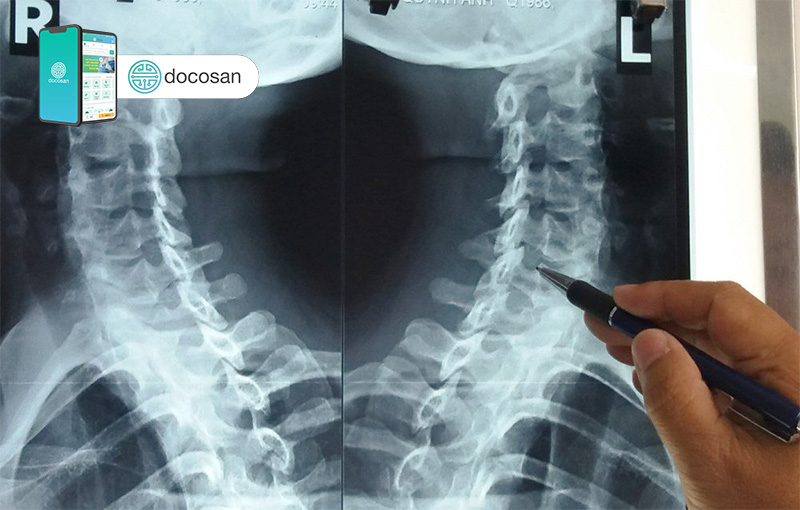

Nếu nghi ngờ người bệnh bị thoái hóa đốt sống cổ, các bác sĩ có thể yêu cầu xét nghiệm hình ảnh và kiểm tra chức năng thần kinh. Một số phương pháp xét nghiệm hình ảnh bao gồm:

- Chụp X-quang